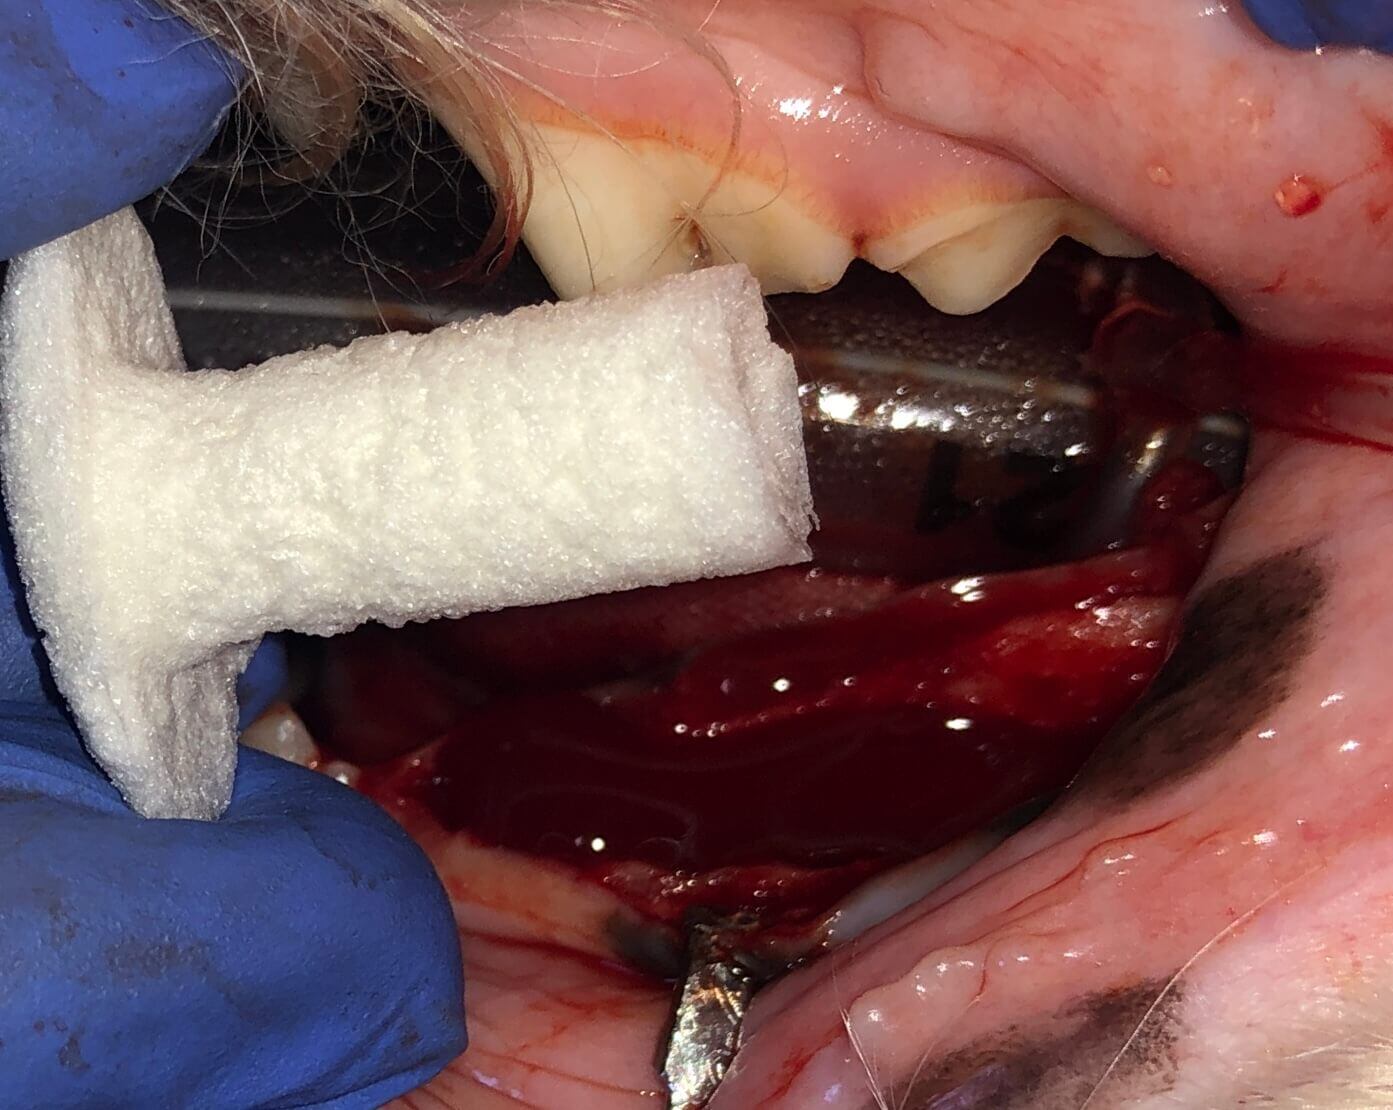

An envelope flap was utilized, followed by curettage to remove granulation tissue and debris. Osteoallograft periomix bone graft material from Veterinary Transplant Services was then placed in the infrabony pocket. Doxirobe was spread thinly to create a membrane covering the graft material, and closure was achieved using 4-0 monocryl to create a tight gingival collar.

The images below were taken at various stages throughout the procedure.

Showing deep bone loss at palatal aspect of upper left canine tooth before an oral nasal fistula has developed

View of the granulation bed which must be fully removed to be able to treat

Also showing some debris, a good lesson to use magnification and clean more

Mixed with blood during GTR procedure

To prevent soft tissue down growth and the bone returns

With tight gingival collar

Envelope flap, section, elevate, graft placement. The site was closed with4-0 monocryl.